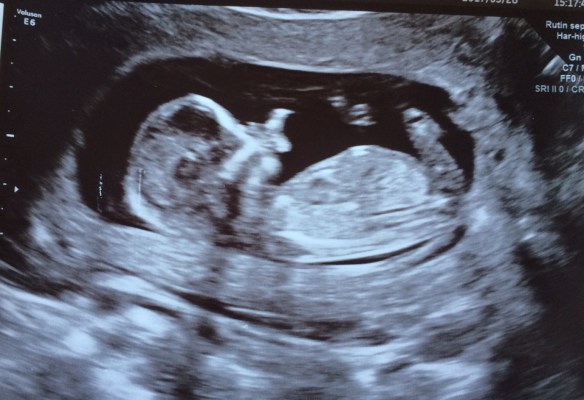

Andra besöket var den 28:e mars då vi gjorde ett tidigt ultraljud för att fastställa leveransdatum lite mer ordentligt. I samma sekund som jag fick ultraljudsmojjängen på magen såg vi en liten bebis i perfekt profil på skärmen, en väldigt häftig känsla. Och ganska obeskrivbar. Hjärtat slog, bebisen fladdrade omkring och vi kunde dessutom se dens tunga när den smakade på lite fostervatten. Tillochmed barnmorskan var lite lyrisk över den väldigt rörliga krabaten som gärna ”visade upp sig”, och det tog ett tag innan hon lyckades få en mätbar bild på den. Men till slut lyckades hon och efter ett par olika mätningar på både kropp och huvud kom vi fram till att vi gissar på att jag var i vecka 13+2, vilket betyder att leveransdatum är 30:e september. ”Mätosäkerheten” är ju dock ganska stor, så vi ska nog inte lägga alltför stor vikt vid just detta datumet. Men så ligger det till i alla fall! Nästa stop i den här resan är på tisdag den 4:e, då ska jag till barnmorskan och ta lite blodprover mm samt boka in det ”vanliga” ultraljudet som man gör omkring vecka 19.

Lilla filuren i tisdags, ca 7-8cm från huvud till rumpa.